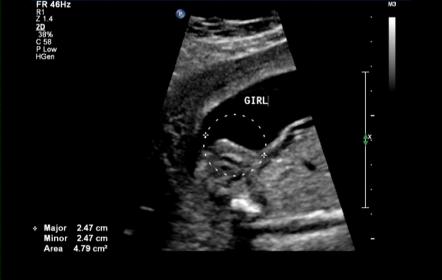

UPDATE!!! Pics included for your confirmation please :)